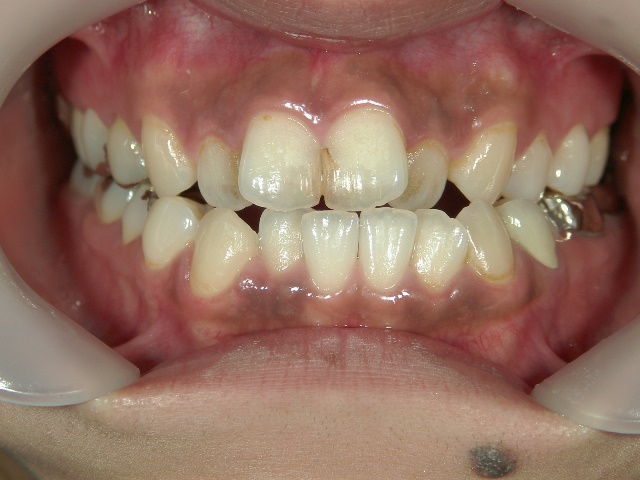

矯正歯科 治療前矯正歯科 治療前

全顎ワイヤー矯正 症例(18)

30歳女性 浜松市北区在住

治療期間3年4ヶ月

主訴:前歯の歯並びが気になる。

矯正歯科 治療前 上顎を装置(QH)で拡大後ワイヤー矯正へ移行、右下5番左下4番 計2本抜歯叢生改善